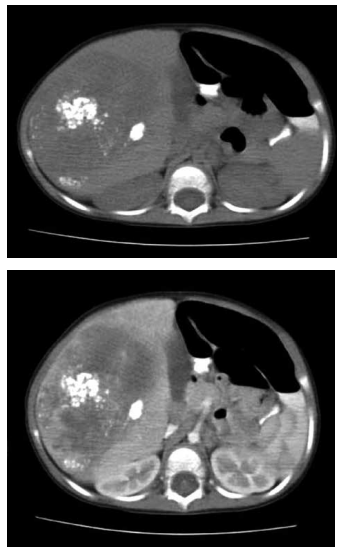

Criança, 18 meses, apresentando massa indolor

palpável no quadrante superior direito do abdome e perda de peso. Solicitados exames laboratoriais demonstrando anemia e elevação de alfafetoproteina (AFP) e

exame de imagem conforme demonstrado abaixo.

A partir do quadro clínico e exame de imagem, pode-se afirmar, EXCETO:

A partir do quadro clínico e exame de imagem, pode-se afirmar, EXCETO: